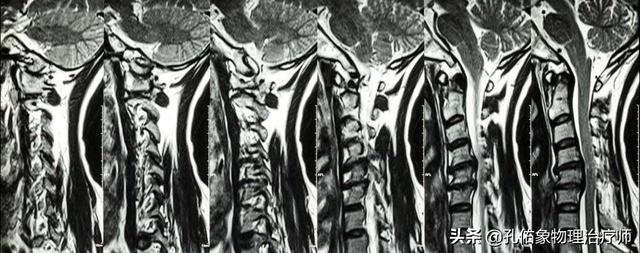

2.脊髓型颈椎病

其发病率低于神经根型颈椎病,约10%-15%,但是这类型的颈椎病在临床上,其重要性腰远远超过神经根型颈椎病,此型颈椎病是最重的。脊髓损害来源于中央后突的髓核,椎体后缘骨赘,增生、肥厚、钙化的后纵韧带、黄韧带压迫,或者是因为血液供应障碍。其病理反射一般都是阳性的,在治疗上一般保守效果不佳,重者尽早手术治疗,特别需要注意的是,此类型颈椎病不宜做牵引或是更多的手法,这是视为禁忌的哈。